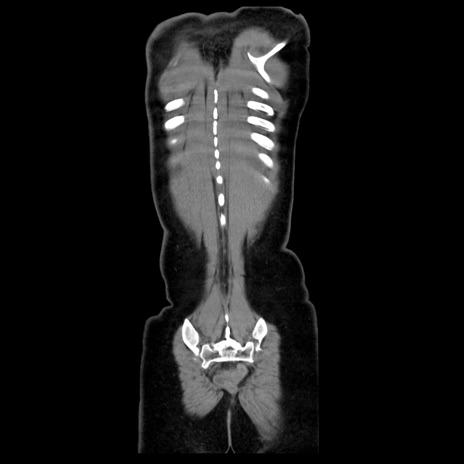

症例39(冠状断像)

CT